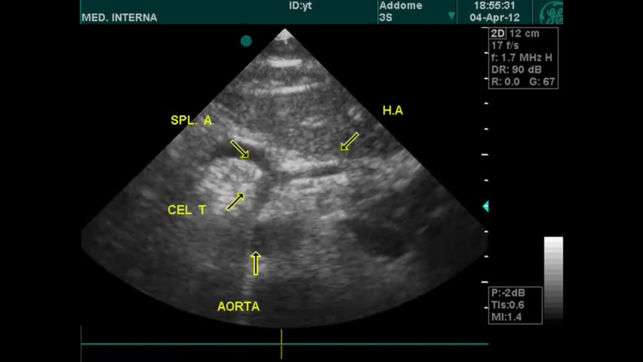

‎请注意,本程式以来自海外的英语放射诊断科视频,提供各种诊断个案,暂时没有提供中/英文字幕。 诊断过程需要优秀的临床技巧,但是,正确应用不同的造影工具,能大大帮助鉴别诊断或证实临床的怀疑。这不应该是”渔翁撒网”式的策略,以一系列的诊断调查表,取代临床技巧。相反,诊断影像的知识,能大大提高诊断过程的水平。 随着科技日新月异,新型医疗仪器不断推陈出新,让医疗专业人员在疾病诊断上,提供极大的帮助。除往日的X光,计算机X射线断层造影术(Computed Tomography, CT),B超(Ultrasound)外,新型的工具包括磁共振显像(MRI),核医学(Nuclear Medicine, NM…